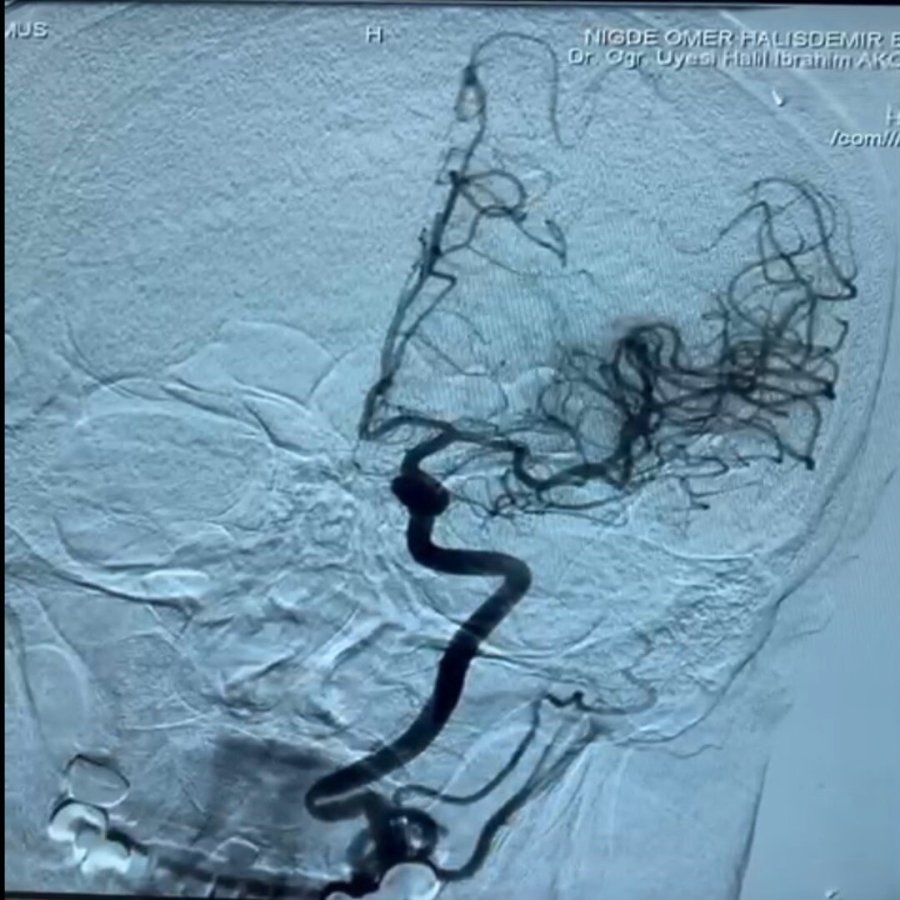

İnmenin, beyin damarlarında tıkanma ya da kanama sonucu felç ve ölüme neden olan ciddi bir sağlık sorunu olduğunu vurgulayan Dr. Akçay, dünya genelinde erişkin yaş grubunda ölümlerin ikinci en sık nedeninin inme olduğunu, nörolojik engelliliğin ise en sık nedeninin yine inme olduğunu ifade etti. Dr. Akça; "İnmelerin yüzde 80'i damar tıkanıklığına bağlı gelişiyor. Diyabet, obezite ve yaşam süresinin uzaması gibi faktörler inme riskini etkiliyor. İnme merkezimizde, hastalara erken dönemde kateter anjiyografi yöntemi ile pıhtı çıkarma ve damardan kan sulandırıcı tedavileri 7/24 uygulanmaktadır. Bu nedenle, tedavide zaman kaybını önlemek amacıyla 112 sağlık hizmetleri, hastane acil servisi ve inme merkezi ekibimiz koordineli bir şekilde çalışmaktadır." dedi.